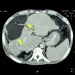

Stage 4 colon cancer refers to cancer that has spread from the inner lining of the colon to other parts of the body. The most common places it spreads are to the liver and lungs. Doctors assign a number to each stage of colon cancer, based on how advanced the cancer is and where it has spread to.

The type of chemotherapy depends on whether the cancer has spread to the liver and what other organs or tissues it might have reached. It might include chemo drugs that travel through the bloodstream or through your lymphatic system. It might also involve ablation, which involves targeting specific areas of the body with radiation.